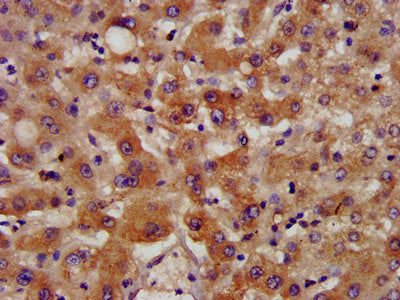

IHC image of NSDHL Antibody diluted at 1:400 and staining in paraffin-embedded human liver tissue performed on a Leica BondTM system. After dewaxing and hydration, antigen retrieval was mediated by high pressure in a citrate buffer (pH 6.0). Section was blocked with 10% normal goat serum 30min at RT. Then primary antibody (1% BSA) was incubated at 4°C overnight. The primary is detected by a biotinylated secondary antibody and visualized using an HRP conjugated SP system.